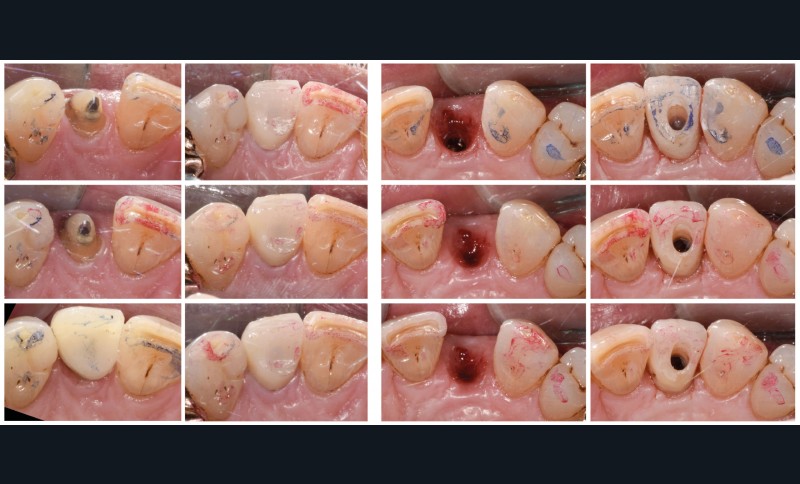

Situation initiale

Un patient de 62 ans se présente en consultation afin de réaliser les coiffes prothétiques des dents 12 et 22. La 12 présente une restauration par prothèse transitoire non adaptée. Un implant au niveau de la 22 a été posé par un autre praticien selon une technique chirurgicale en deux temps. Le praticien a adressé le patient pour la réalisation prothétique. L’option de bridge collé cantilever mono ailette n’avait pas été retenue ou proposée selon une technique chirurgicale en deux temps. Le patient souhaite rétablir l’esthétique et la fonction de ces deux dents uniquement.